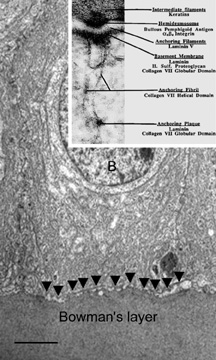

The anterior surface of the human cornea is covered by a transparent, nonkeratinized, stratified (five- to seven-cell layer) squamous epithelium uniformly around 50 μm in thickness that is continuous with the epithelium of the limbus and conjunctiva (Figs. 1, 2, and 3). The basal corneal epithelial cells actively secrete extracellular material (type IV collagen, laminin, heparin, and small amounts of fibronectin and fibrin) that forms an underlying 75-nm thick basement membrane called the basal lamina. On electron microscopy, the morphology of basal lamina appears to be composed of two distinct layers: a 25-nm thick lamina lucida and a 50 nm thick lamina densa (Fig. 3).

Fig. 3. Transmission electron micrograph (3,500×) of the central corneal epithelium with a summary diagram (inset). Microvilli project from the anterior corneal surface into the tear film. S, squamous cells; W, wing cells; B, basal epithelial cells. Bar = 1 μm. (Inset modified from Hogan MJ, et al. Histology of the human eye. Philadelphia, WB Saunders, 1971.)

The cytoplasm of a corneal epithelial cell primarily contains cytoskeletal intermediate filaments and has sparse cytoplasmic organelles (i.e., mitochondria, endoplasmic reticulum, and golgi apparatus). The predominant cytoplasmic filament is keratin, whereas actin and microtubules are two other major types found in corneal epithelial cells. The epithelial cells are held together to one another by numerous anchoring junctions called desmosomes, whereas the basal surface of the epithelium adheres to the basal lamina and underlying Bowman's layer through aa adhesion complex composed of hemidesmosomes, anchoring fibrils (type VII collagen), and anchoring plaques (Fig. 4). The function of the corneal epithelium is twofold: (a) to form a barrier from the environment to the corneal stroma of the cornea, and (b) to form a smooth refractive surface on the cornea through interaction with the tear film.

Fig. 4. Transmission electron micrograph (10,000×) of a basal epithelial cell showing the adhesion complexes (arrowheads) that anchor it in place onto the Bowman's layer and summary inset. B, basal epithelial cell. Bar = 1 μm. (Inset from Albert and Jakobiec: Principles and practice of ophthalmology. Philadelphia, WB Saunders, 2000.)